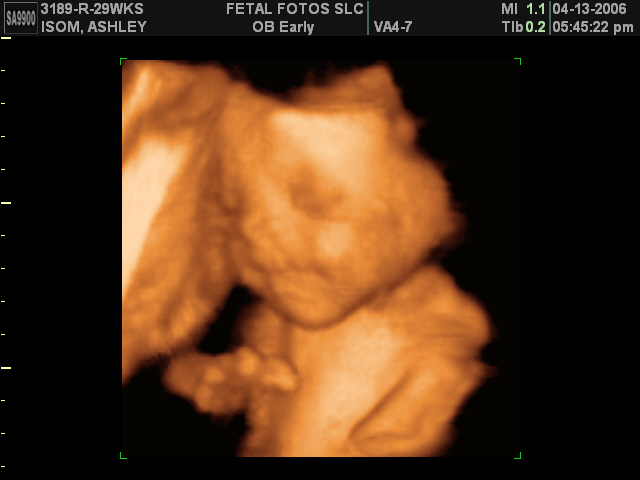

I was very excited to get Kamdyns 3D ultrasound done not only to see him but to compare his to Jaydan and Madysons 3D pictures too. I found their cds of all their 3D pictures and I am amazed at not only how much they look alike but also how they all act alike. They all did alot of the same behaviors in their ultrasounds. For example they all have a picture of them rubbing their eye. They all have one with their hands up by their face and mouth. They all had obsessions with their hands by their faces. It was so fun to compare them. Now I cant wait to see him in person and see how much he really looks like them as a newborn!

Kamdyn face shot